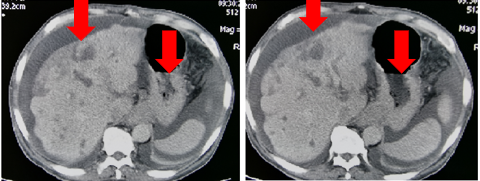

发病后CT(外院2017.11):贲门胃底部溃疡性肿物考虑恶性,腹腔多发肿大淋巴结,考虑转移。

图表1-1:发病后CT(外院2017.11)